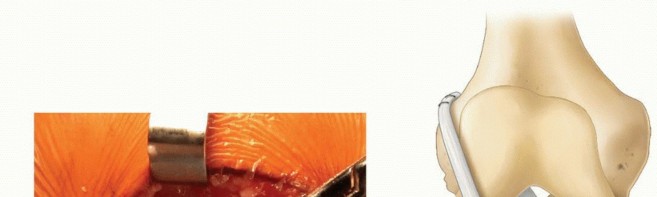

The anterior and posterior borders of the iliotibial band are incised and the incisions carried proximally under the skin using curved meniscotomes ( TECH FIG 1A ).

The iliotibial band is detached proximally under the skin using a curved meniscotome or an open tendon stripper. Alternatively, a counterincision can be made at the upper thigh to release the tendon.

Dissection is performed distally to separate the iliotibial band from the joint capsule and from the lateral patellar retinaculum ( TECH FIG 1B ).

The iliotibial band is left attached distally at the tubercle of Gerdy ( TECH FIG 1C ).

The free proximal end of the iliotibial band is tubularized with a no. 5 Ethibond whipstitch and wrapped in a moist sponge until needed later. -

TECH FIG 1 • Harvest of iliotibial band graft for physeal-sparing ACL reconstruction. The anterior and posterior aspects of the iliotibial band are identified through a laterally based incision at the knee. A. A meniscotome or an open tendon stripper is then used to harvest the proximal aspect of the graft. B. The graft is then freed distally. C. The free proximal aspect of the graft is tubularized and left attached distally to the tubercle of Gerdy. (A,B: From Kocher MS, Weiss JM. ACL reconstruction in the skeletally

immature patient. In: Tolo VT, Scaggs DL, eds. Master Techniques in Orthopaedic Surgery: Pediatrics. Philadelphia: Lippincott Williams & Wilkins, 2008:277-287.)